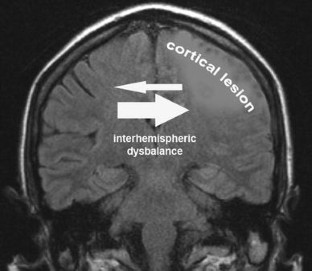

Fig. 2